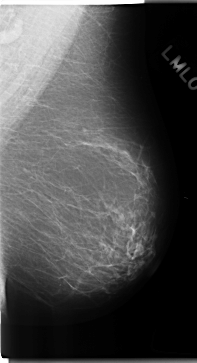

C_0192_1.LEFT_MLO

LEFT_MLO LINES 4712 PIXELS_PER_LINE 2552 BITS_PER_PIXEL 12 RESOLUTION 50 NON_OVERLAY